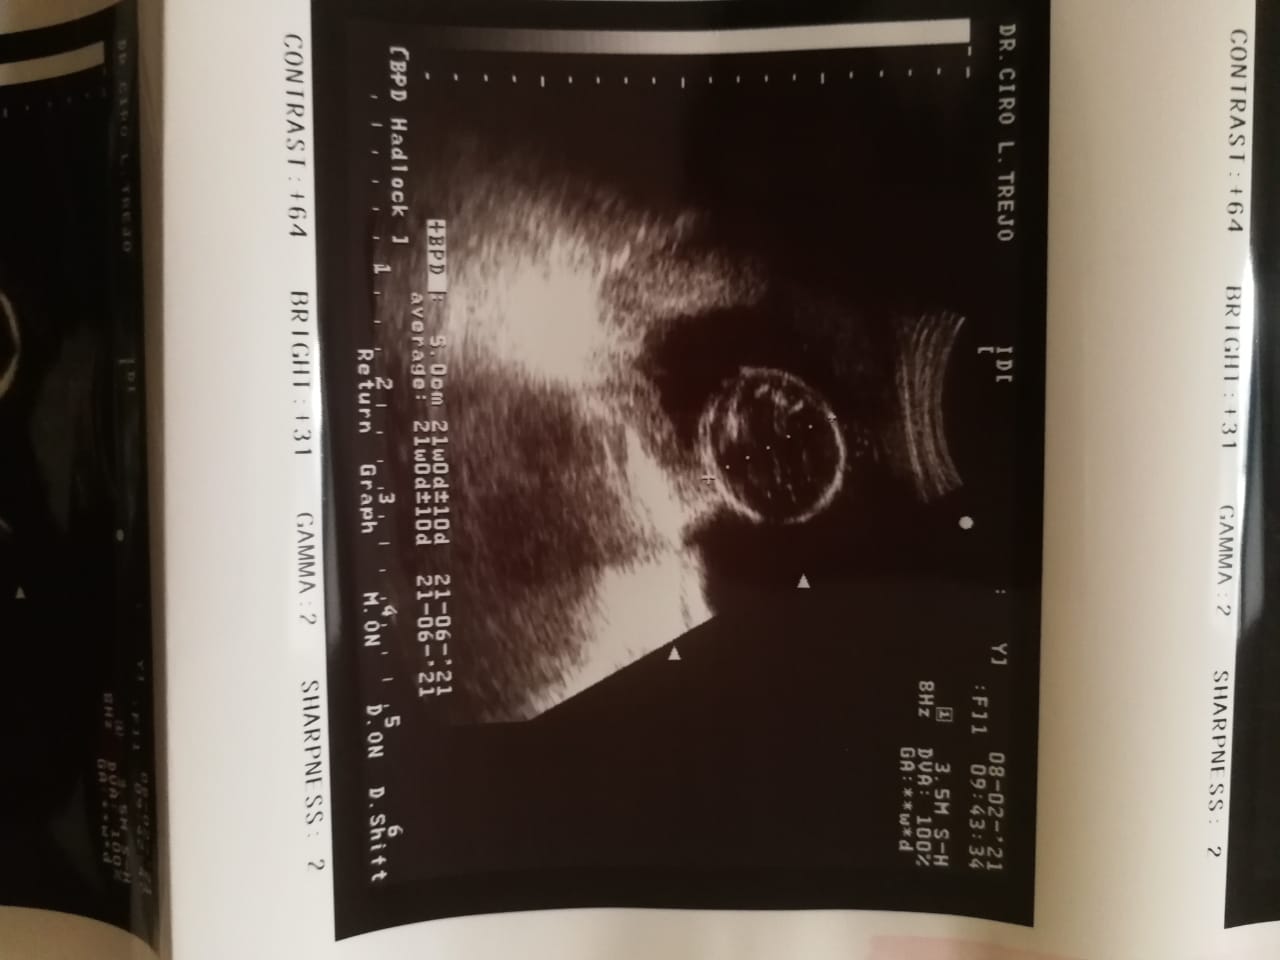

I’ve been pregnant four times. Each time we found out, we were overjoyed—filled with hope and excitement. But that happiness was always cut short. Every single pregnancy ended in miscarriage. The pain is indescribable. Each loss sent me into a deep depression, grieving the baby we had already begun to love. Through it all, my husband has been my rock, holding me up and reminding me not to give up on our dream.